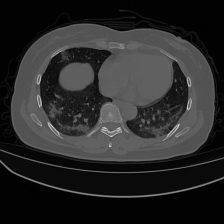

Figure 7 consists of the visualization of three examples masks using our approach and the comparison architectures for multi-classes Covid-19 segmentation. The first example shows a mixture case of GGO and Consolidation, where most of the infected regions consist of consolidation and small GGO regions are attached to the consolidation regions. Unlike the masks of the comparison architectures, the mask of our approach has a high similarity to the ground truth mask for both the consolidation and GGO classes. The second and third examples also represent a case where both GGO and consolidation are present in both lungs. The infected regions with consolidation are mainly in the lower lobes of both lungs and GGO spreads in both lungs with peripheral and posterior distribution. The masks of these examples confirm the observation in the first example, as the predicted masks of D-TrAttUnet show a high similarity to the GT masks for both infection types GGO and Consolidation.

Refer to caption Refer to caption Refer to caption Refer to caption Refer to caption Refer to caption Refer to caption

Slice AttUnet SCOATNet MISSFormer UCTransNet D-TrAttUnet GT

Figure 7: Visual comparison of a segmentation model trained with different segmentation architectures for Multi-classes (No-infection, GGO and Consolidation) Covid-19 infection segmentation using Dataset_2. GGO is presented by the Green color and Consolidation by the red color.